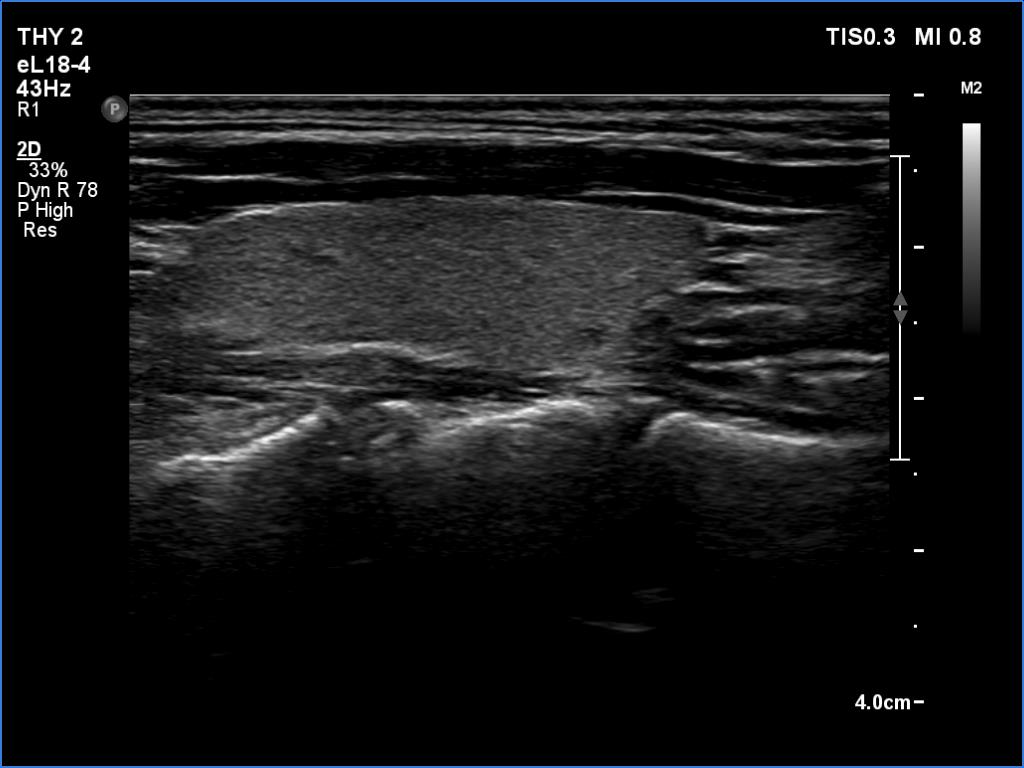

Case 1348 (ultrasonographic picture 6)

Left lobe, longitudinal scan.